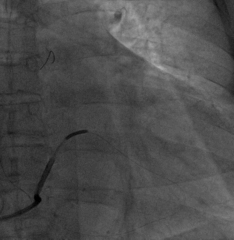

6225i球囊造影可见轻微夹层,远端未显影

6250VIS鞘管直接造影可见分支显示良好

AP

LAO